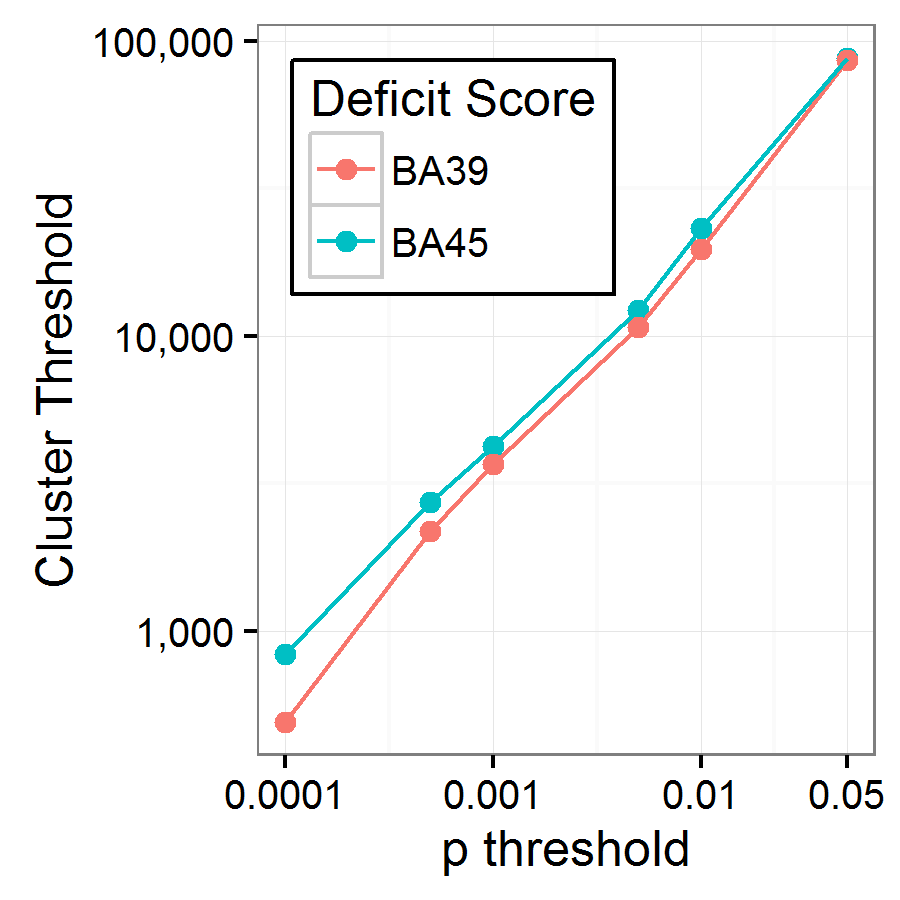

The relationship between cluster size threshold (95th percentile of maximum cluster sizes across 1000 permutations) and p-threshold is shown in Figure 3. This analysis produced the expected positive relationship between p-threshold and cluster size threshold: more permissive p-thresholds allow more voxels into the cluster analysis, thus producing larger clusters. Indeed, the relationship is almost perfectly linear in the log-log plot in Figure 3. Analysis of false positives is trivial here because, by definition, 95% of permutations had 0 clusters larger than the cluster size threshold.

The next stage was evaluating how well this method recovers the true neural correlates for each deficit score. It was immediately apparent that only the most conservative p-threshold (0.0001) produced a viable cluster size threshold. The next most conservative threshold (0.0005) produced cluster size thresholds of more than 2000 voxels; at p-threshold 0.01, the cluster size threshold was above 10,000 voxels. Any clusters of that size or larger would not be neuroanatomically specific enough to provide useful insights into lesion-symptom relationships.